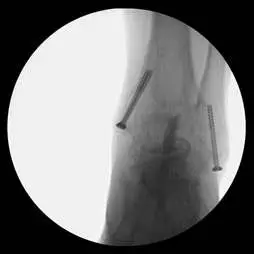

These are pics of the implant being placed in the ankle joint